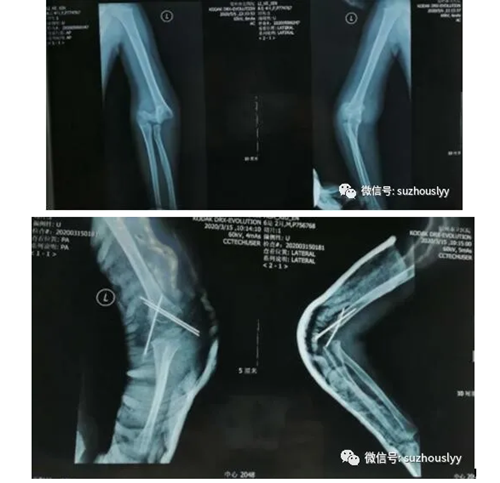

随着夏季的到来,人们户外运动逐渐增多,很多家长带着自己的小宝宝外出游玩,在享受美好惬意的闲暇时,危险往往不期而至,由于儿童天性活泼好动,且缺乏一定的危险自我保护意识,因此受伤导致的骨折并不少见,其中肱骨髁上骨折是儿童肘部的严重损伤,也是最常见的儿童肘部骨折,约占全部肘关节损伤的50%~70%,常见于3~10岁的儿童。肱骨髁上骨折在治疗上强调早期闭合复位。既往采用闭合手法复位,成功后用极度屈曲位石膏固定才有可能维持复位,往往在进行石膏固定的操作过程中或之后即出现再度移位,而且极度屈曲位石膏固定容易造成患肢极度肿胀,进一步则可发展为前臂缺血性挛缩,不仅成功率低,而且容易带来不同程度的并发症。闭合复位经皮穿钉技术在儿童肱骨髁上骨折的应用可谓是治疗上的一大进步。该方法的优点是:穿针固定牢固;创伤小;不易发生肘内翻畸形;可早期功能锻炼;且患儿痛苦少、住院时间短花费少,是治疗儿童肱骨髁上骨折的良好方法。

我院骨三科为了加强儿童骨折的诊治能力,专门安排医师纵成成外出进修学习,现进修回来将近一年,在杨主任的带领下,使我科的儿童骨折诊治水平有了长足的进步,尤其对于儿童肱骨髁上骨折微创治疗,彻底改变了过去患儿来到医院后等肿胀形成再消肿手术的传统模式。对于健康的儿童,入院后2小时内,由于此时患儿肘部肿胀尚未达到高峰,我们皆急诊给予手法复位闭式复位内固定手术治疗,不仅明显减轻了患儿的痛苦,缩短了住院了时间,降低了费用,而且具有不留瘢痕,肘关节功能恢复佳等优点。